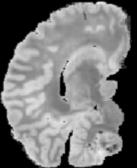

In neuroimaging, MRI tissue properties characterize underlying neurobiology, provide quantitative biomarkers for neurological disease detection and analysis, and can be used to synthesize arbitrary MRI contrasts. Estimating tissue properties from a single scan session using a protocol available on all clinical scanners promises to reduce scan time and cost, enable quantitative analysis in routine clinical scans and provide scan-independent biomarkers of disease. However, existing tissue properties estimation methods - most often $\mathbf{T_1}$ relaxation, $\mathbf{T_2^*}$ relaxation, and proton density ($\mathbf{PD}$) - require data from multiple scan sessions and cannot estimate all properties from a single clinically available MRI protocol such as the multiecho MRI scan. In addition, the widespread use of non-standard acquisition parameters across clinical imaging sites require estimation methods that can generalize across varying scanner parameters. However, existing learning methods are acquisition protocol specific and cannot estimate from heterogenous clinical data from different imaging sites. In this work we propose an unsupervised deep-learning strategy that employs MRI physics to estimate all three tissue properties from a single multiecho MRI scan session, and generalizes across varying acquisition parameters. The proposed strategy optimizes accurate synthesis of new MRI contrasts from estimated latent tissue properties, enabling unsupervised training, we also employ random acquisition parameters during training to achieve acquisition generalization. We provide the first demonstration of estimating all tissue properties from a single multiecho scan session. We demonstrate improved accuracy and generalizability for tissue property estimation and MRI synthesis.